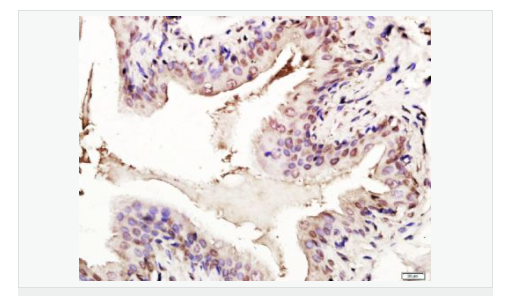

| 產(chǎn)品應(yīng)用 | WB=1:1000-2000 ELISA=1:1000-5000 IHC-P=1:100-500 IHC-F=1:100-500 Flow-Cyt=1ug/Test ICC=1:100-500 IF=1:100-500 (石蠟切片需做抗原修復(fù)) not yet tested in other applications. optimal dilutions/concentrations should be determined by the end user. |